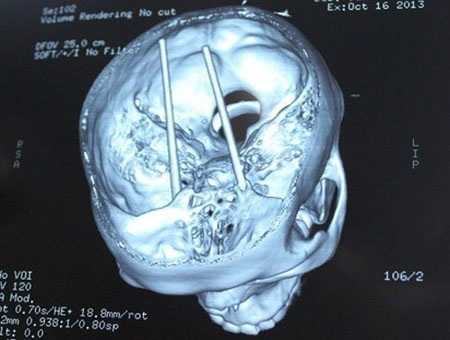

| Hai chiếc đũa xuyên qua mắt tới sàn não của anh Dũng. Ảnh: TG |

Phim chụp CT cho thấy, toàn bộ hai chiếc đũa dài khoảng 18cm đã cắm ngập xuyên từ hốc mắt qua sàn sọ, xuyên vào thân não. Theo bác sĩ Nguyễn Kim Chung - Phó Trưởng Khoa Ngoại thần kinh (Bệnh viện Chợ Rẫy): “Đây là ca nặng nhất trong các trường hợp bị đũa đâm vào đầu mà chúng tôi tiếp nhận từ đầu năm đến nay. Ca phẫu thuật kéo dài hơn 5 giờ đồng hồ mới kết thúc”.

Bác sĩ Chung cho biết thêm, các bác sĩ đã phẫu thuật từ đường hốc mắt vào để rút đũa ra. Bệnh nhân không có máu bầm trong não nhưng đã bị dập não nên vẫn bị xuất huyết dọc đường đi của đũa. Rất may, các mạch máu lớn không bị đũa chọc thủng nên bệnh nhân được bảo toàn mạng sống.